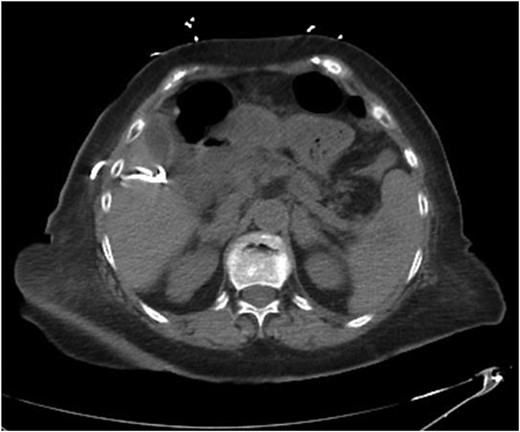

Repeat imaging was performed and revealed peri-hepatic ascites, significant anasarca and bilateral pleural effusions (Fig. 3) while the PCT remained in good position (Fig. 4). Bilateral chest tube placement and drainage of the pleural effusions revealed chylothorax and malignant cells. Cultures of both PCT output at the time of insertion and pleural fluid cultures grew no organisms.

Computed tomography (CT) chest demonstrating bilateral pleural effusions.